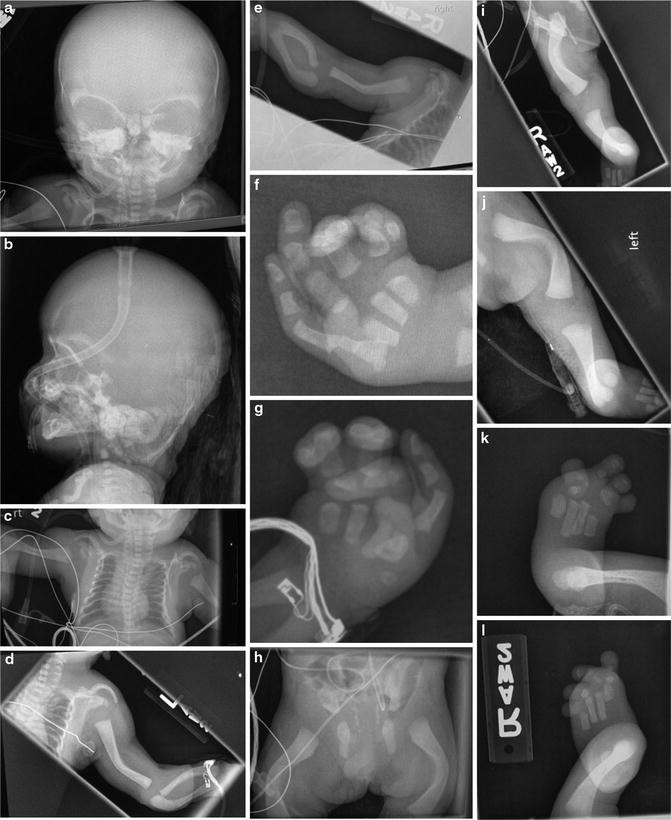

Figure 1 From Oto Palato Digital Syndrome With Swvere X Ray Changes In Two Half Brothers Semantic Scholar

Figure 2 From Oto Palato Digital Syndrome With Swvere X Ray Changes In Two Half Brothers Semantic Scholar